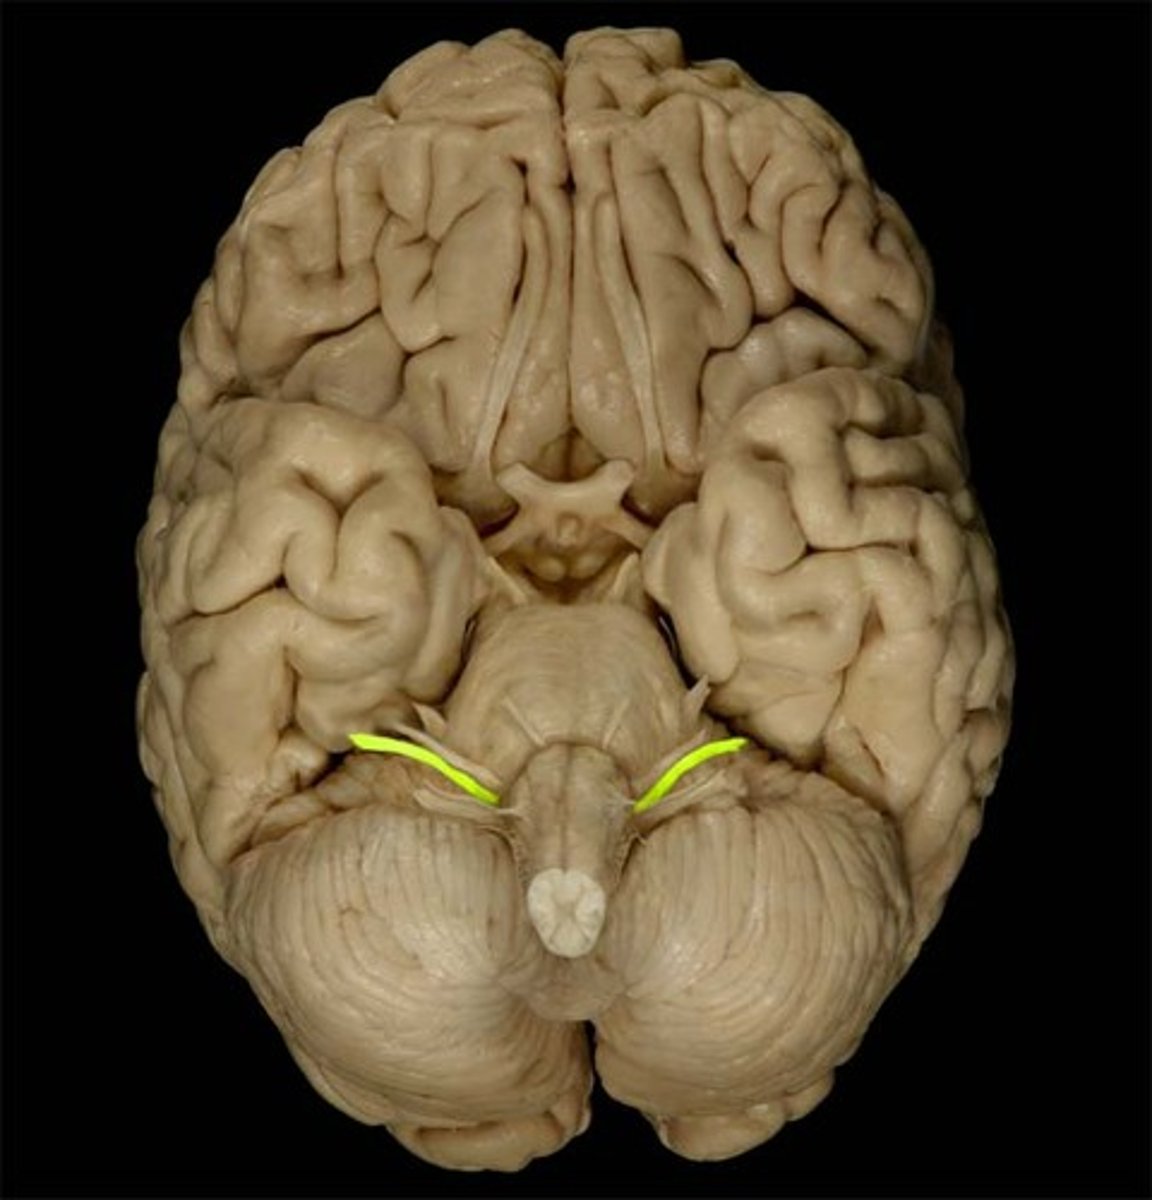

medulla oblongata

most inferior part of the brain stem; regulates breathing, heart rate, & blood pressure

the 'olives'

oval-shaped structures located on the anterior surface of the medulla, lateral to the pyramids

accessory nerves

controls swallowing via vagus nerves

hypoglossal nerves

controls tongue movement; speech